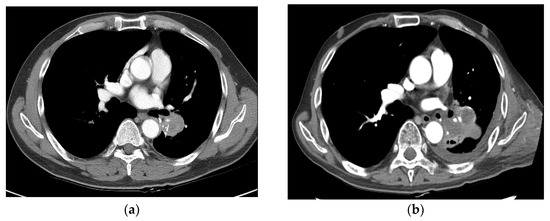

3.5. PD and a Case of Fatal Hemoptysis

| 19 | Yes | No | No | 105.6 | Grade 5 massive hemoptysis (6 months after SBRT) |

| 19 | 68, M | 6.3 | Primary | Pneumoconiosis, COPD, old Tb (40 years ago) | ex-smoker (30 PY) | cT2N0M0 | LUL | SqCC | Lt pneumonectomy | 29.0 | 55 Gy/10 fx | PR |